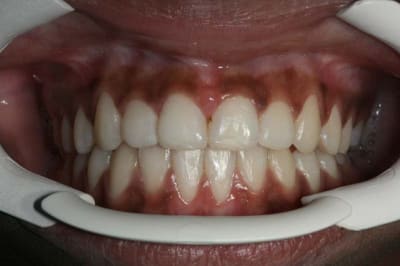

voici l'état de la gencive en fin de TTT. ORTHO

3 kemn9r - Eugenol

La question que je me pose est :

dois-je épaissir cette gencive très fine, (donc fragile), en face de 31/41 ?

@+ Bjc.

bonsoir ,s'il fallait greffer tous les jeunes patients qui finissent l'ortho avec une gencive comme ceci c a d: fine mais pas de tension des freins, on n'arrêterait pas.

maintenant,si on veut appliquer le sacro- saint principe de précaution ......tout est permis